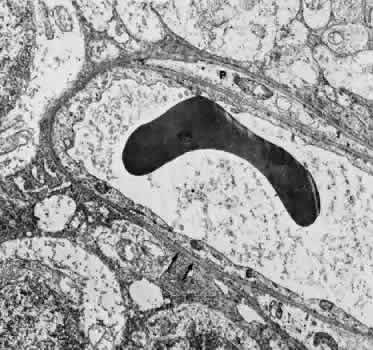

Venules are usually less than 20 μm in diameter.15 The media is composed of a single layer of cells resembling pericytes, containing poorly developed myofilaments and dense bodies. Elastin is not present. The adventitia contains little other than the basement membrane surrounding the pericyte (Fig. 5).

Fig. 5. Electron micrograph of a human retinal venule. E, endothelial cell. The pericyte (P) contains abundant mitochondria and rough-surfaced endoplasmic reticulum. Pinocytotic vesicles are present, and the myofilaments are poorly developed.